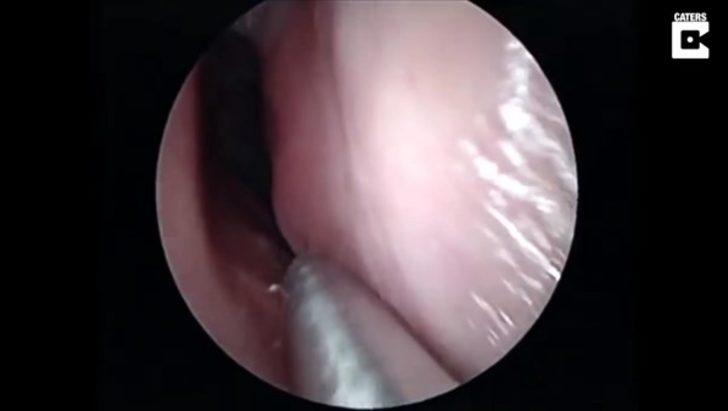

Burnunda garip bir hareketlilik hisseden hasta doktora göründü.

Doktor ise ufak bir operasyon yaptı.

Yüzerken burnuna kaçan şey doktorları bile şaşırttı